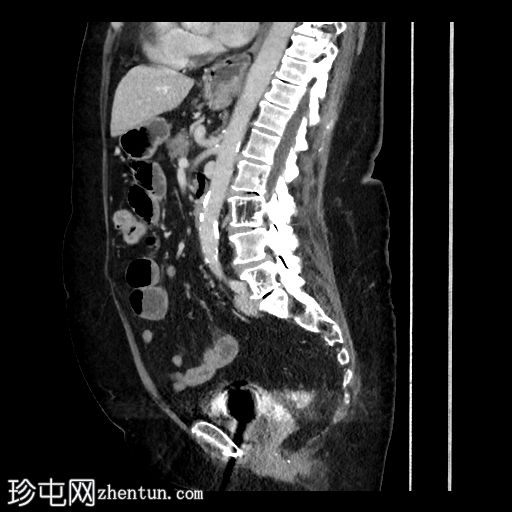

冠状位增强扫描(门静脉期)

可见小食管裂孔疝。胆道积气。胆囊增厚,相对减压,并伴有胆囊十二指肠瘘。空肠至回肠近端中度扩张,回肠近端可见节段性增厚,并延伸至右下腹的移行点。移行点处可见一枚卵圆形层状胆结石,周围有少量吞咽物。双侧全髋关节置换术导致盆腔出现条状伪影。未见其他急性异常。

这是一个典型的胆石性肠梗阻病例,伴有胆囊十二指肠瘘,移行点位于右下腹近端回肠(里格勒三联征)。请注意,肠壁在移行点附近轻度增厚,阻塞性胆结石可能与吞咽物混杂在一起,容易被忽略。此外,还应注意胆囊肠瘘可能被误认为是正常的上消化道解剖结构或十二指肠憩室。这些观察结果有助于强调全面检查的重要性。